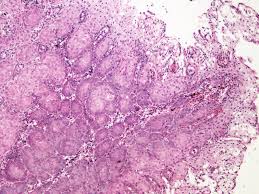

The area of overlap (between squamous & columnar) is known as the transformation zone. There are two types of cells that line the cervix, one lines the outer cervix (portio) and another lines the inner cervix (endocervix). This process can be studied over time by serial examinations of the cervix. Hpv is a sexually transmitted disease. Low grade squamous intraepithelial lesion (lsil/cin 1). There is a distinct junction between the two cell types called the transformation zone. As for the transformation zone. The squamous epithelium is stratified and nonkeratinizing. One of the fears of hpv infection is that it can turn into cervical cancer. Rare cases may harbor in situ or invasive squamous or glandular lesions. The anatomy of the cervix is summarized in chapter 1.the colposcopic appearances of normal squamous epithelium, columnar epithelium, squamocolumnar junction, immature and mature metaplasia and the congenital transformation zone are described in this chapter. Benign cervical tissue (transformation zone with squamous metaplasia and benign endocervical glands. Histology of the normal cervix:

The latter often show large areas of metaplastic squamous epithelium and the development of an atypical transformation zone. The whole mucosa, including the crypts and the supporting stroma, is displaced in ectropion. Diagnosis of cervical squamous metaplasia. Benign cervical tissue (transformation zone with squamous metaplasia and benign endocervical glands. During metaplasia, columnar epithelium is transformed into mature squamous epithelium. Squamous metaplasia of uterine cervix is diagnosed in following ways: The interf ace between these two epithelium types is dynamic, and later is the site of the transformation zone. One of the fears of hpv infection is that it can turn into cervical cancer. Clinical significance of squamous metaplasia in the cervix in the cervix, the area of the epithelium that has undergone metaplastic change is called the transformation zone (tz). Theoretically, these cells of the transformation zone are vulnerable to dna damage and mutational changes during this replicative process. The area of overlap (between squamous & columnar) is known as the transformation zone. Cervical carcinogenesis associated with hpv primarily affects metaplastic squamous epithelium in a specific anatomical location, the transformation zone. What is the transformation zone?

This process can be studied over time by serial examinations of the cervix. During metaplasia, columnar epithelium is transformed into mature squamous epithelium. Benign cervical tissue (transformation zone with squamous metaplasia and benign endocervical glands. The squamous epithelium is stratified and nonkeratinizing. The latter often show large areas of metaplastic squamous epithelium and the development of an atypical transformation zone. It is in this transformation zone that abnormal growth or dysplasia develops. The transformation zone the zone of past and present squamous metaplasia: There was broad agreement that the tz is the area where squamous metaplasia has occurred. There is a distinct junction between the two cell types called the transformation zone. Also known as transition zone. Chronic inflammation, surface erosion and reactive epithelial changes are common. With acetic acid, these areas become pale to glassy with a membranous appearance. Cervical carcinogenesis associated with hpv primarily affects metaplastic squamous epithelium in a specific anatomical location, the transformation zone.